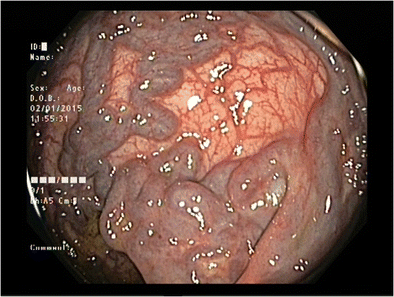

Anorectal varices arise secondary to backflow of blood in collateral submucosal vessels. The primary cause of anorectal varices is portal hypertension. Due to easy access, anorectal varices are easy to manage. The cornerstone of management is treatment of underlying factors causing portal hypertension. Other treatment options include suturing, ligation, and portosystemic shunting. Reference: https://en.wikipedia.org/wiki/Anorectal_varices Image via https://link.springer.com/article/10.1007/s12664-015-0567-2